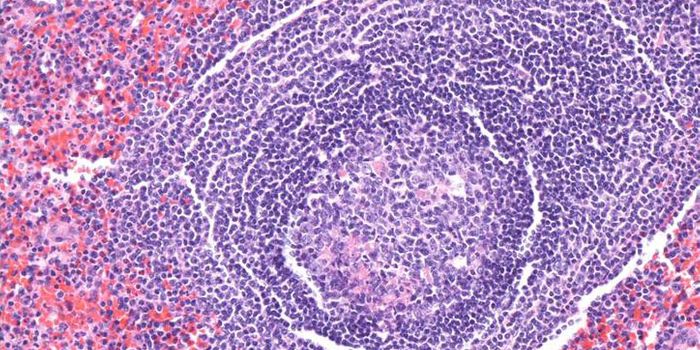

FEB 12, 2016ImmunologyAcute lymphoblastic leukemia (ALL) and non-Hodgkin’s Lymphoma (NHL) affect 75,000 and 72,000 people each year in t ...

MAR 18, 2015Immunology

After a chance observation in the lab, researchers found a method that can force dangerous leukemia cells in the l ... -